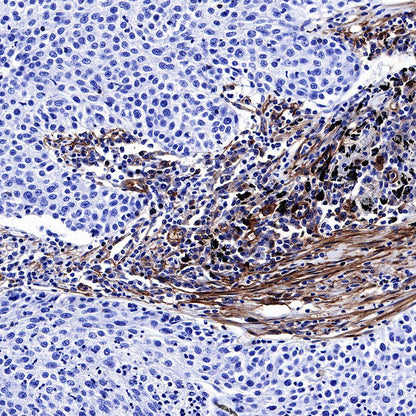

IHC shows positive staining in paraffin-embedded human lung squamous carcinoma. Anti-CD39 antibody was used at 1/500 dilution, followed by a HRP Polymer for Mouse & Rabbit IgG (ready to use). Counterstained with hematoxylin. Heat mediated antigen retrieval with Tris/EDTA buffer pH9.0 was performed before commencing with IHC staining protocol.